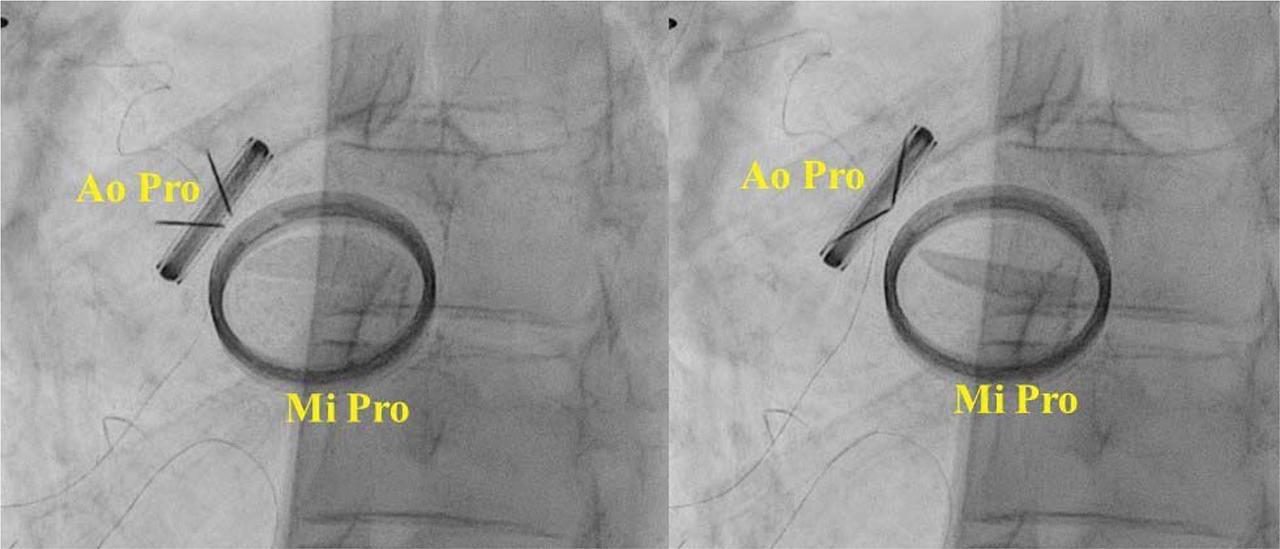

Figure 2